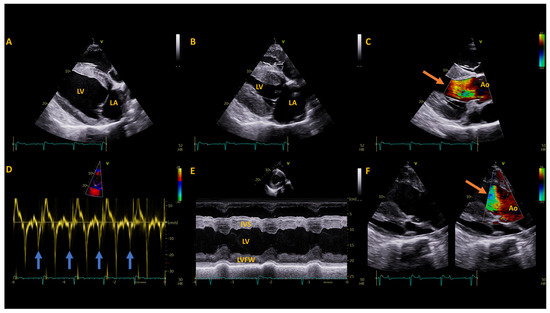

| Measurement (Units) | Available References (mean ± SD) | Pre-Operative | 1 Year Post-Operative | 2 Years Post-Operative |

|---|---|---|---|---|

| Left Atrium | ||||

| LAAmax (cm2) | 92.8 ± 5.0 | 71.4 | 71.8 | 70.9 |

| LADmax (R) (cm) | 11.9 ± 0.7 | 10 | 10.4 | 9.8 |

| LA FAC active (%) | 20 ± 7.0 | 41 | 34 | 30 |

| LADmax (L) (cm) | 12.9 ± 0.5 | 13.3 | 13.1 | 11.2 |

| LAAmax sx (cm2) | 108.8 ± 12.2 | 102.9 | 87.4 | 74.6 |

| LA/Ao (Sx) Ratio | 2.5 ± 0.3 | 2.7 | 2.2 | 2.1 |

| Left Ventricle | ||||

| IVSd (cm) | 2.8 ± 0.3 * | 3.2 | 3.3 | 2.7 |

| LVIDd (cm) | 11.1 ± 1.5 * | 9 | 8.9 | 9.0 |

| LVFWd (cm) | 3.3 ± 0.3 * | 2.6 | 2.6 | 2.8 |

| IVSs (cm) | 4.4 ± 0.4 | 5 | 4.7 | 4.4 |

| LVIDs (cm) | 6.7 ± 1.3 * | 4.2 | 4.6 | 5.0 |

| LVFWs (cm) | 4.4 ± 0.4 | 4.3 | 3.9 | 3.9 |

| FS (%) | 40.4 ± 5.7 * | 54 | 49 | 44 |

| LVIVd (ml) | 1475 ± 200.7 | 694 | 672 | 757 |

| LVIVs (ml) | 412 ± 81.6 | 146 | 148 | 189 |

| SV (mL) | 1065 ± 139.2 | 548 | 524 | 568 |

| CO (L) | 37.1 ± 6.02 | 30.6 | 30.4 | 21.2 |

| EF (%) | 71 ± 4.9 | 79 | 78 | 75 |

| MWT (cm) | 3.05 ± 0.2 * | 2.9 | 2.9 | 2.8 |

| RWT | 0.52 ± 0.2 * | 0.65 | 0.66 | 0.61 |

| LAD/LVID ratio | 1.1 ± 0.1 | 1.11 | 1.17 | 1.09 |

| HR (bpm) | 38 ± 4.4 * | 50 | 57 | 37 |

| Great Vessels | ||||

| PADed (cm) | 6.5 ± 0.47 | 5.8 | 5.8 | 5.9 |

| AoDed (cm) | 7.0 ± 0.9 * | 6.6 | 6.7 | 6.5 |

| PAed-sx (cm) | 5.0 ± 0.31 | 4.1 | 4.1 | 4.7 |

| AoAsx (cm2) | 45 ± 5.5 | 38 | 39.5 | 36 |

| Ao/PA (sx) Ratio | 1.4 ± 0.1 | 1.6 | 1.6 | 1.4 |

| Tissue Doppler Imaging | ||||

| IMP | 0.38 | 0.29 | 0.44 | |

| Em/Am | 3.1 ± 0.8 | 1.7 | 1.2 | 1.9 |

| Velocity | ||||

| AoVmax (m/s) | 1.1 | 1.2 | 0.9 |